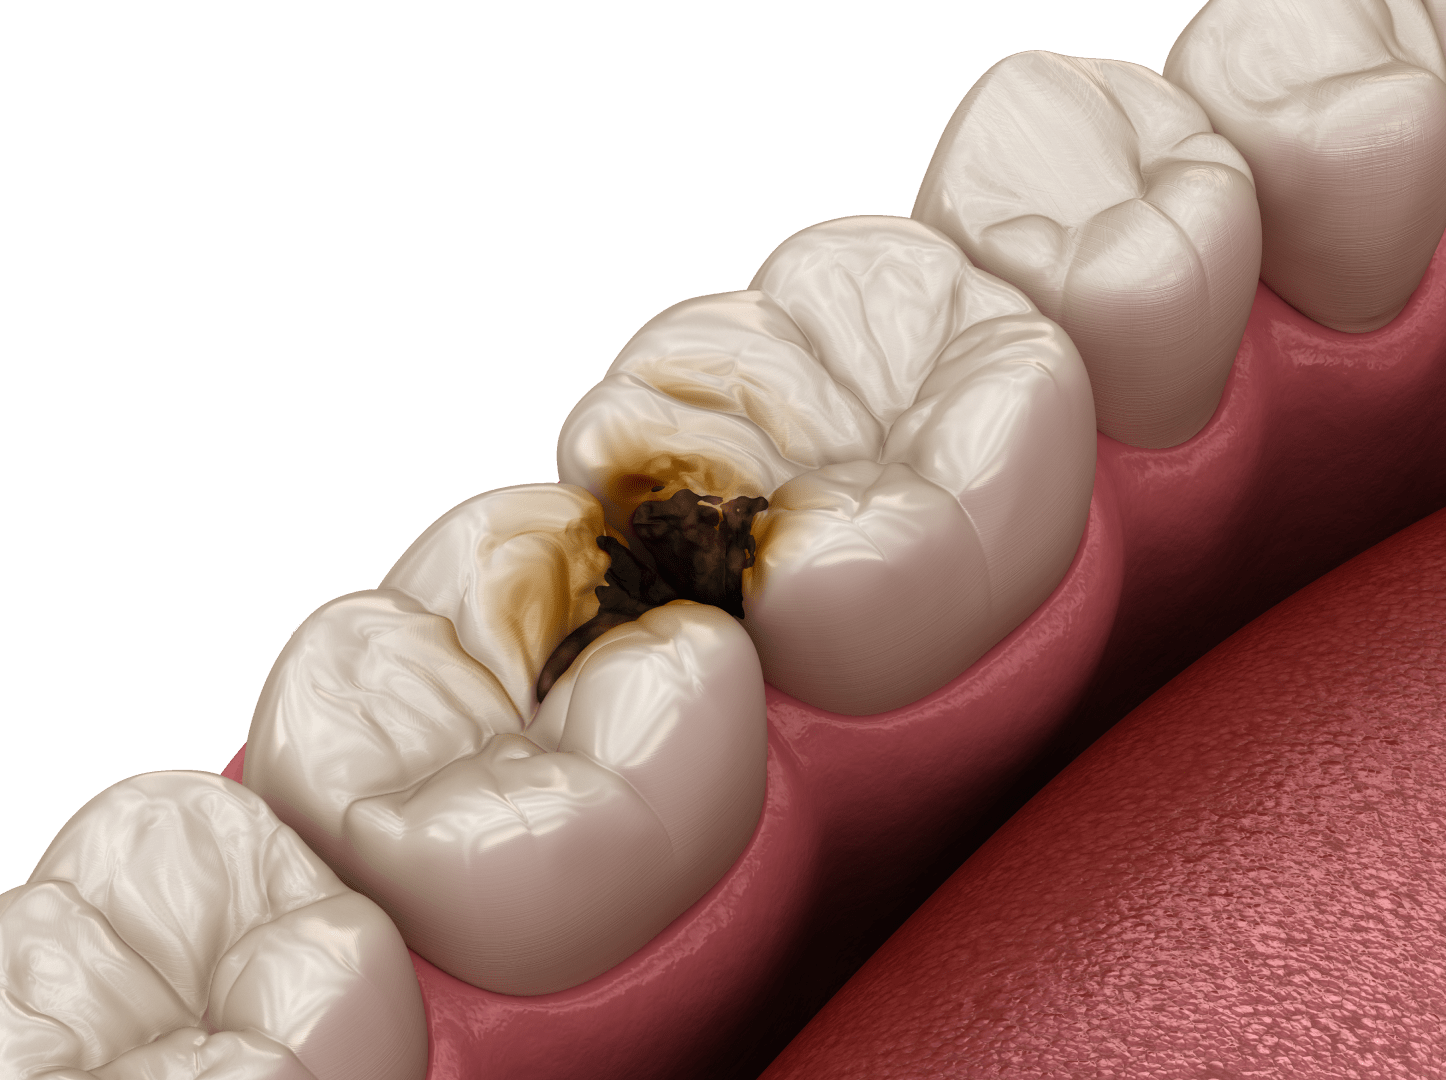

Лікування карієсу та інших стоматологічних захворювань

Усі інфекційно-запальні захворювання ротової порожнини мають бути усунені перед імплантацією. Основна небезпека в даному випадку – це інфекційний компонент, який присутній при карієсігінгівітістоматитіпульпітіперіодонтіті та інших захворюваннях. При установці імплантів за таких умов висока ймовірність занесення інфекції всередину рани, що може спричинити відторгнення імпланту.

Карієс